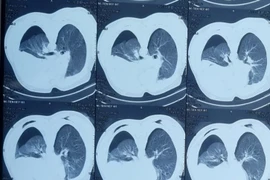

ANTD.VN - Ngày 10-4, Bệnh viện Trung ương Quân đội 108 thông tin, các bác sĩ viện này vừa cấp cứu một bệnh nhân nguy kịch vì biến chứng cúm A, phải chạy tim phổi nhân tạo ECMO.